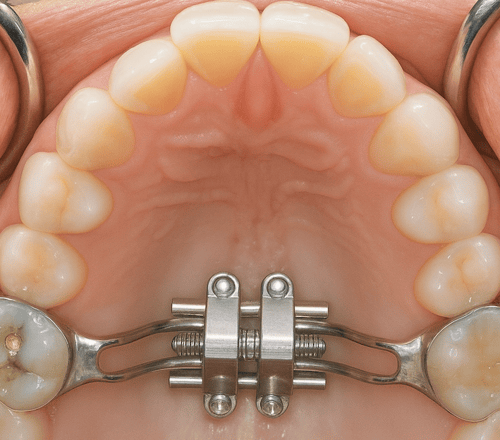

15-18 歲:治療策略需依孩子骨年齡決定

針對 15–18 歲青少年,上顎骨縫已經初步癒合,但我們會根據骨骼成熟度與個別條件,選擇最適合的擴弓方式;在接近成年、骨骼較緊密的情況,通常我們會採用「迷你骨釘輔助擴弓」(MARPE),讓擴展更穩定、更接近真正的骨性改變,而不是單純移動牙齒的假性擴弓。更重要的是,我們會同步評估孩子的呼吸與氣道狀況。因為真正理想的矯正,不只是讓牙齒整齊,而是讓孩子能夠用鼻子順暢呼吸、睡得更好、臉型更平衡發展。

隱適美擴弓裝置 (Invisalign Palatal Expander)

這是隱適美(Invisalign)近年推出的新系統,專為處於混合齒列期的兒童(一、二期矯正)設計。

- 運作原理: 採用特殊的 3D 列印醫用材料,整套牙托本身就具備了擴張路徑。它是透過牙齒的位移帶動骨骼調整。重點在於它不需要「轉螺絲」,而是像換隱形牙套一樣,更換不同進度的擴弓牙托。

- 舒適度: 異物感極低,沒有金屬支架,對口腔黏膜較友善,且幾乎不影響發音。

- 優點: 數位化精準預測、外觀隱形、方便摘下清潔、家長無需手動操作。

- 缺點: 價格通常較高。